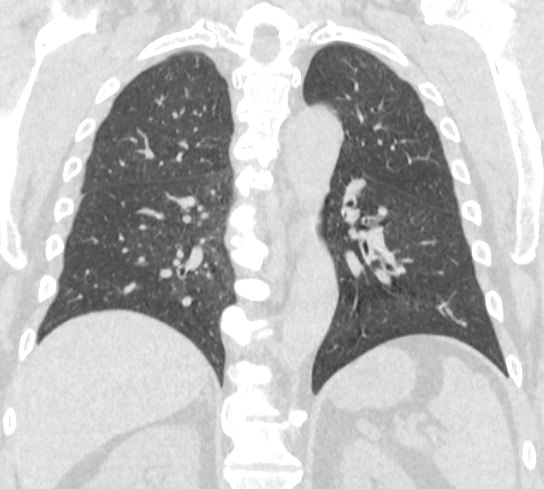

Информативность МСКТ органов грудной клетки дополняет функциональная проба, то есть методика проведения сканирования на вдохе (инспираторная КТ) и на выдохе (экспираторная КТ). При выполнении КТ на вдохе с задержкой дыхания удается добиться максимального контраста между наполненными воздухом легкими и более плотными структурами, такими как плевра, стенки бронхов и кровеносные сосуды. Кроме того, на фоне пневматизированных легких хорошо видны очаговые и диффузные патологические изменения.

При экспираторной пробе (пробе на выдохе) можно выявить воздушные ловушки (то есть стойкое повышение пневматизации легочной ткани) на фоне пневмонитов, бронхиолитов, обструктивных заболеваний легких, эмфиземы.